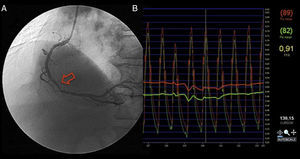

Verificou-se a ocorrência de uma morte súbita, seis meses após cateterismo, à qual se atribuiu causa cardíaca, apesar de não se ter efetuado autópsia. Tratava-se de um doente de 65 anos com lesões de 50% na descendente anterior proximal e de 40% após origem da circunflexa. A avaliação por FFR foi de 0,84 na lesão da DA e 0,98 na lesão da Cx, pelo que se optou por manter em terapêutica médica (Figura 1).